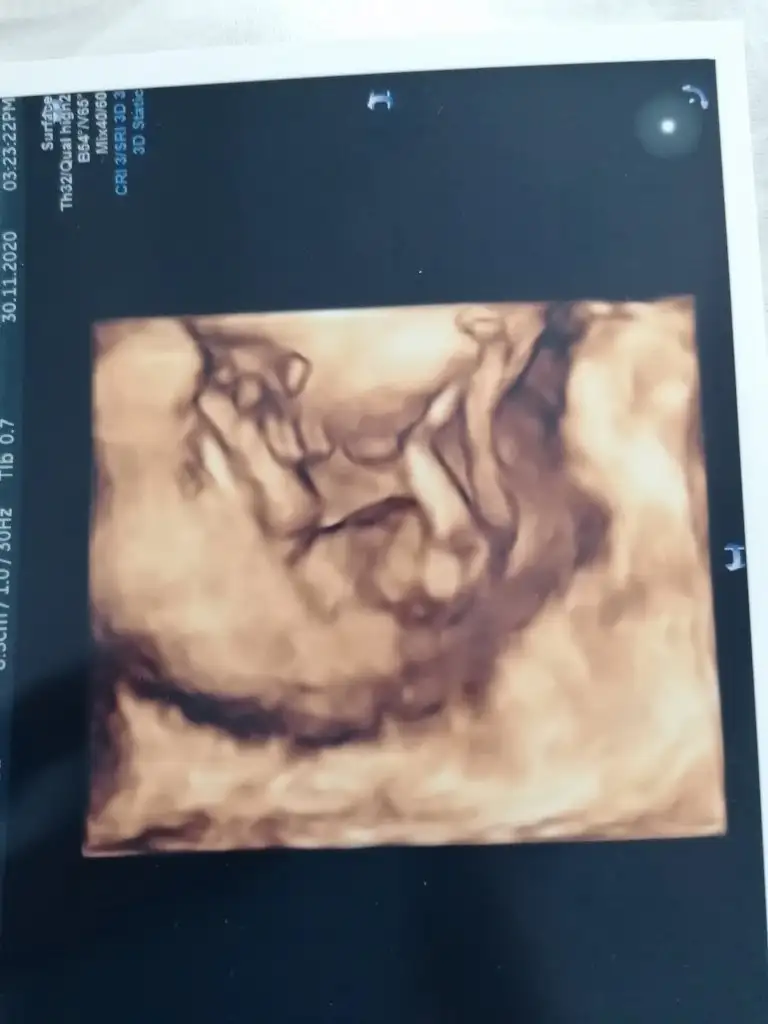

Amin canım tüm minikler sağlıkla gelsin bebeisin ultrason resmini atar misin sende bakim benim minnos seninkine mi benziyo Seraa0606 nin bebeğininemi

Bu 2 hafta önceki hali ilk kıza benziyor dediği hali bugün boydan vermedi dr kafasıyla kolunun resmini verdi kaynanamda bu resmine erkeğe benziyor demisti